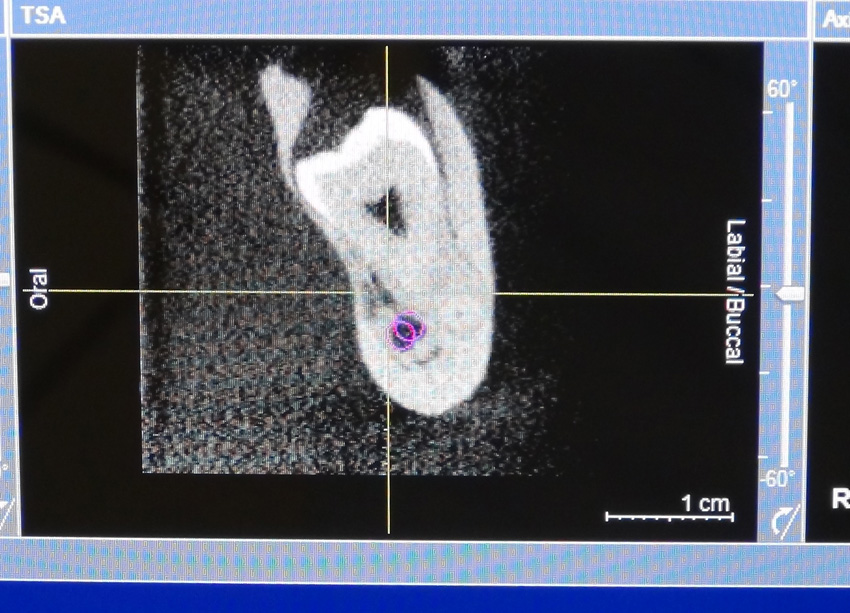

Allerdings bieten wir hier auch die Option einer kompletten digitalen 3D Planung an.